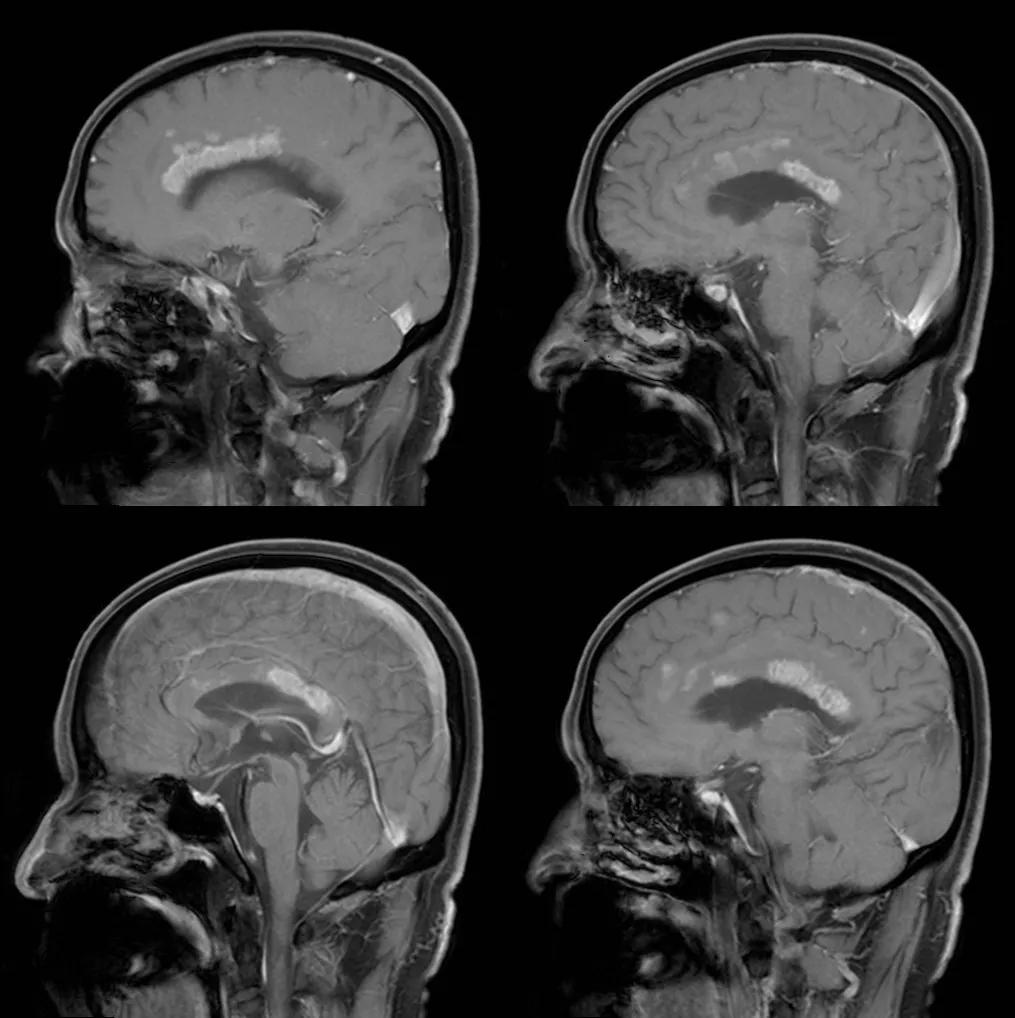

- 急性期表现为胼胝体弥漫性肿胀,T1WI呈稍低信号,T2WI及FLAIR呈稍高信号,以矢状位观察最佳,可单独累及胼胝体压部或整个胼胝体,DWI呈高信号,ADC图呈低信号,部分患者可观察到脑室周围白质或内囊受累,少见皮层受累,表现为扩散受限,不强化和强化病例均可见到。如果增强扫描可见胼胝体有不同程度强化,呈小灶状或不规则斑片状,系血脑屏障破坏所致(如本例),本例患者处于急性期。

- 随着病变进展至亚急性期和慢性期,胼胝体内可出现坏死、囊变,以膝部及压部表现为著。在膝部和体部常表现为中心夹层状异常信号,类似“三明治”状,其境界清楚,据认为这是本病的特点之一。病理检查证实,病变主要对称性侵及胼胝体的中心层,而背、腹层面的组织结构相对完好。主要的组织学所见为脱髓鞘,少突胶质细胞明显减少,而含脂巨细胞大量增多。部分病例在T2加权像上,偶见胼胝体变性、坏死区内出现极低信号,镜下病理显示含脂巨细胞内可见散在或成堆的含铁血黄素分布,可能为T2异常低信号的病理基础。

上排:原发性胼胝体变性急性期

下排:原发性胼胝体变性慢性期,表现为胼胝体萎缩、软化

急性期原发性胼胝体变性(胼胝体压部及体部病变,CT呈低密度,T1WI呈稍低信号,FLAIR呈稍高信号,扩散受限)向慢性期转变,慢性期胼胝体压部病灶出现坏死或囊变,FLAIR呈低信号